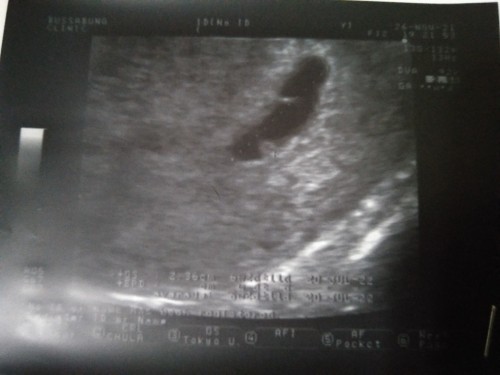

วันนี้ไปซาวด์มารอบที่สอง เจอแค่ถุงกับก้อนเล็กแต่ยังไม่เจอการเต้นของหัวใจเรย แต่คุณหมอก็ยังไม่คอนเฟิร์มให้เพราะว่าเหมือนการเจริญเติบโตช้ากว่าปกติ หรือว่าท้องยังอ่อนอยู่ค่ะ ซาวด์รอบสองแล้ว คิดหนักกว่าเดิม กลัวว่าเขาจะหยุดการเจริญเติบโตไว้แค่นี้ #ท้องแรกคะ #คุณแม่คนไหนเคยเป็นบ้างค่ะ#ขอคำแนะนำหน่อยค่ะ #ขอบคุณสำหรับคำตอบค่ะ